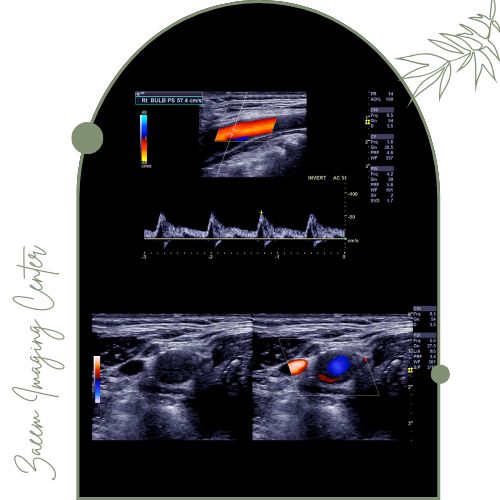

مرکز تصویربرداری پزشکی زعیم تحت مدیریت دکتر علیرضا سرزعیم (فلوشیپ مداخلهای) با همکاری دکتر سمیه زارعی و دکتر مهرناز راسته خدمات تخصصی سونوگرافی رنگی داپلر را با بهرهگیری از جدیدترین فناوریها ارائه میکند. این تیم با تسلط بر تکنیکهای روز دنیا قادر است طیف وسیعی از بیماریهای عروقی و قلبی را تشخیص دهد و به کمک گزارشهای دقیق درمان بیماران را تسهیل نماید.تجهیزات پیشرفته مرکز

در این مرکز دستگاههای نسل جدید سونوگرافی مطابق استانداردهای جهانی مورد استفاده قرار میگیرند. این تجهیزات قادرند در مدت زمان کوتاه تصاویری با وضوح بالا از جریان خون در عروق بدن تهیه کرده و با تحلیل پیشرفته دادهها جزئیترین اختلالات عروقی و قلبی را نمایان سازند.اطلاعات جمعآوری شده توسط تیم پزشکی مرکز بهصورت تخصصی تفسیر و گزارش میشوند تا بهترین مسیر درمان برای هر بیمار انتخاب شود.